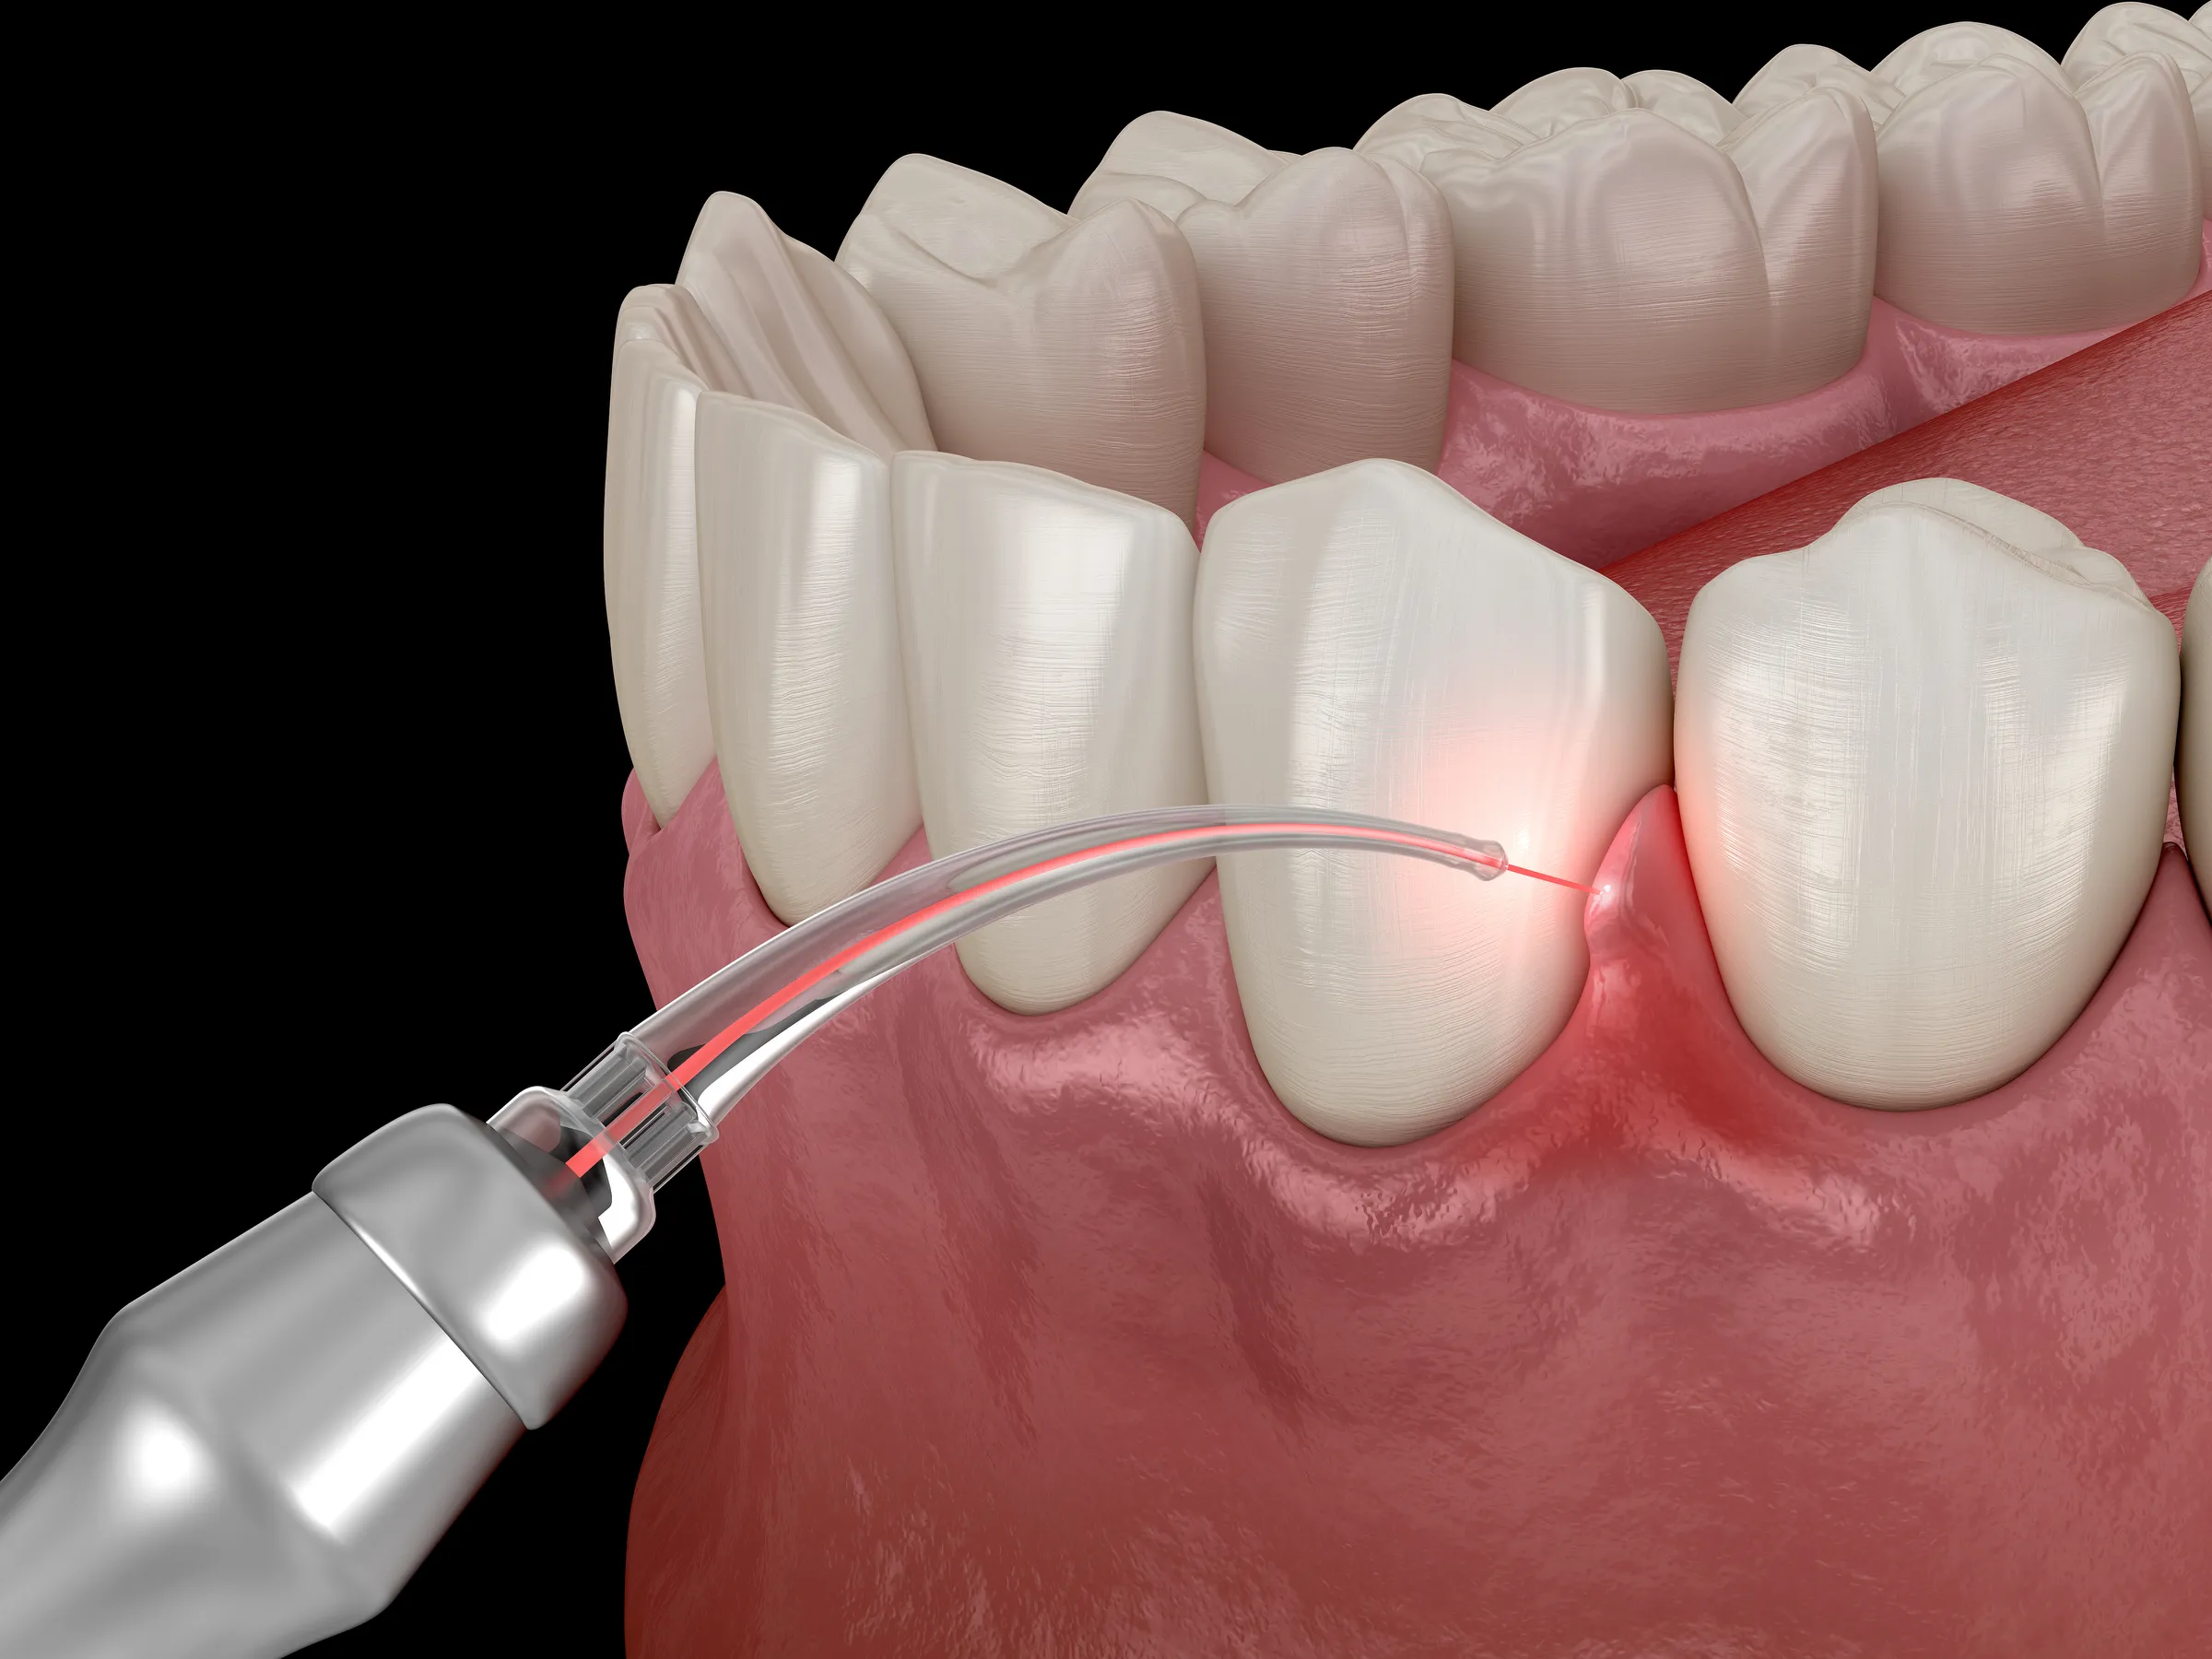

Laser gum surgery is a modern approach to treating gum disease and periodontal concerns. Using focused laser energy, infected tissue and harmful bacteria are carefully removed while preserving healthy gum structure. This minimally invasive technique helps reduce discomfort and supports faster healing compared to traditional methods.

Laser technology allows for more precise treatment, improving both comfort and outcomes for patients with gum disease.

- Precise Treatment Targets infected tissue while preserving surrounding healthy gums.